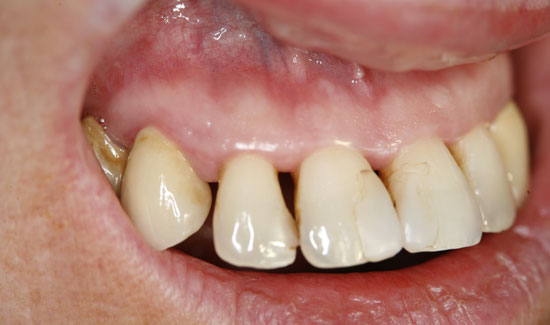

We are reporting on the successful treatment of an advanced case of Parodontitis marginalis profunda in the frontal area of the upper jaw of a 42-year old female patient with local application of ozone gas with the Prozone of W&H. Svea Baumgarten, Dr. med. dent., M Sc, accredited implantologist shares her experiences with ozone treatment.

The patient introduced herself at our practice, inquiring about preserving the front teeth of her upper jaw, which were suffering from chronic periodontitis. We discovered general formation of pockets

(> 10 mm), spontaneous bleeding and a degree of tooth mobility of 2/3, i.e. the teeth were candidates to be extracted. As an interim solution (it was a public holiday) until restoration could take place, we offered local ozone gas treatment.